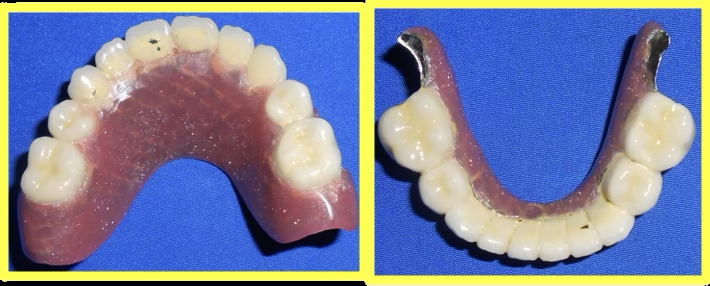

Final result

Upper and lower telescopic removable metallic PFM prosthesis was carefully fitted, adjusted, and delivered to restore complete dental function and aesthetics.